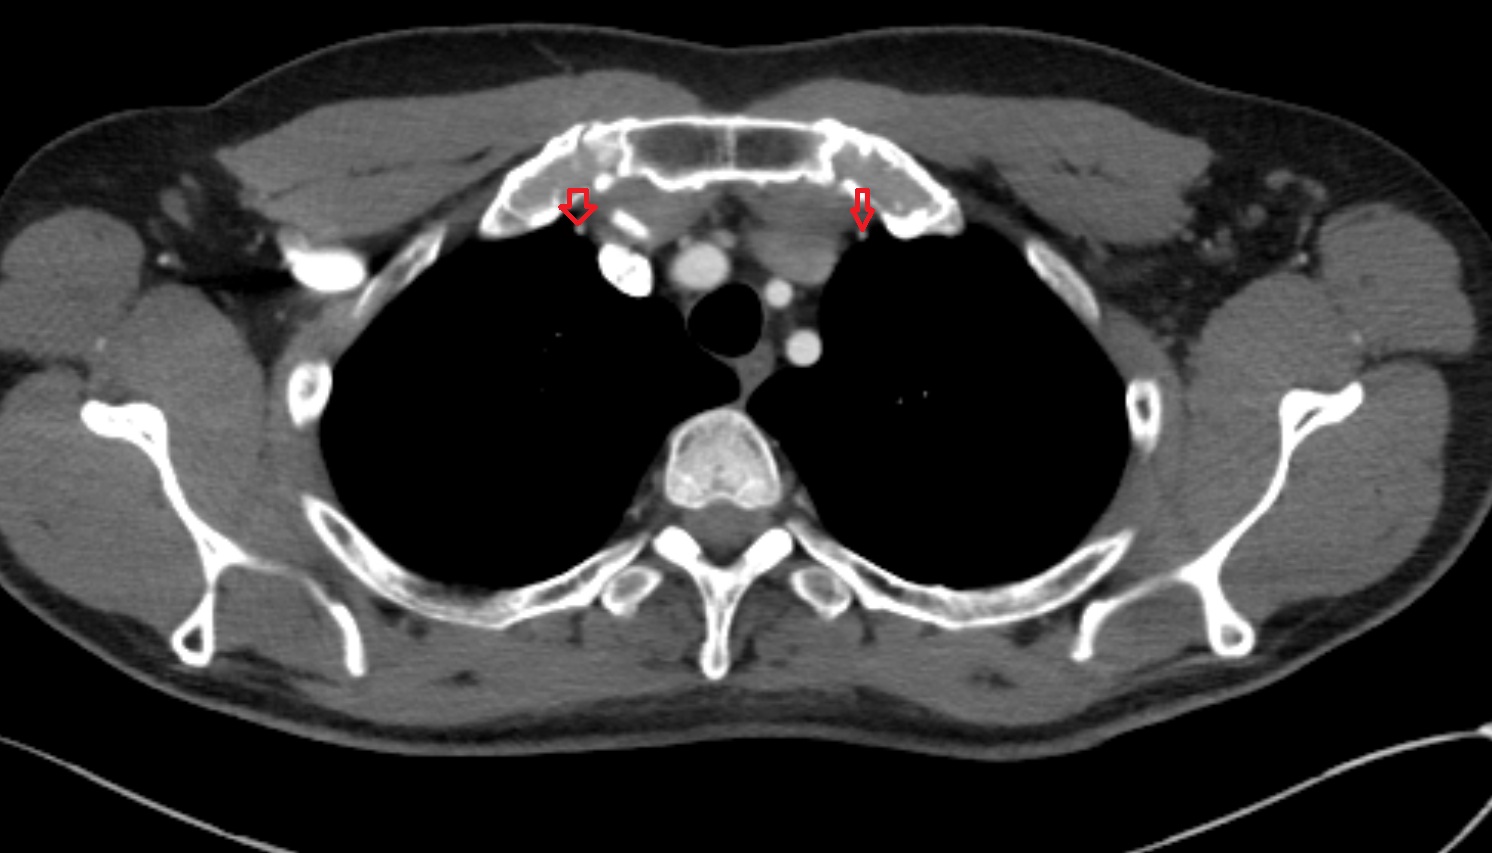

- Thymus